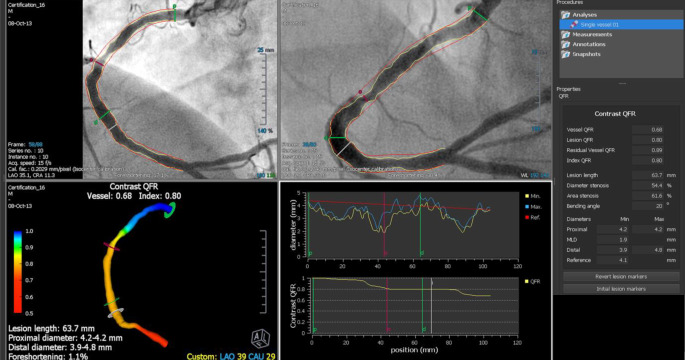

In der Leitlinie werden ein Stenosegrad >50 % der LAD sowie ein Ischämieareal >10 % als prognostisch relevant eingestuft, was jedoch durch die kürzlich publizierte ISCHEMIA-Studie infrage gestellt wird [63]. In allen Fällen mit einem Stenosegrad <90 % muss der Nachweis einer Ischämie durch nichtinvasive Untersuchungen erbracht werden bzw. eine positive iFR/RFR/DFR/FFR-Messung vorliegen.